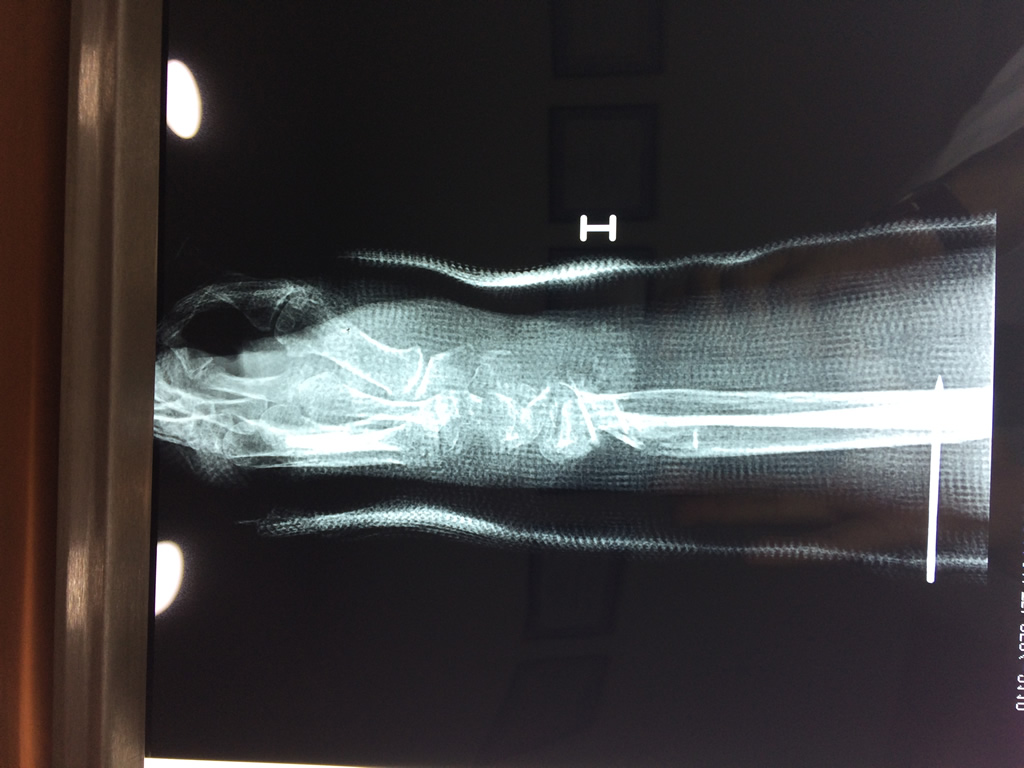

Cirugías de Hombros - Cirugías de Muñecas y Manos

Los procedimientos más comunes en cirugía de la mano son aquellos destinados a reparar traumatismos, incluyendo lesiones de tendones, nervios, vasos sanguíneos, y articulaciones; huesos fracturados; y quemaduras, cortes, y otros daños de la piel.